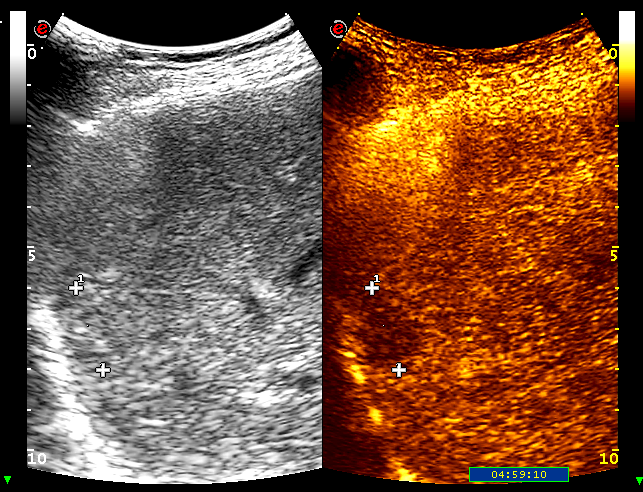

La steatosi epatica

Il fegato grasso è una condizione molto comune. Quando severa può comportare dei rischi per la funzione del fegato.